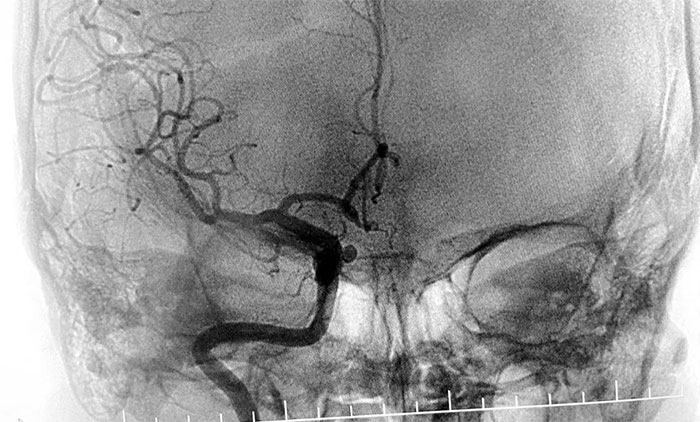

患者入院后,余志良主任為患者完善查體,根據(jù)病情特點,著重排查腦血管疾病可能。通過CTA檢查,發(fā)現(xiàn)右側(cè)頸內(nèi)動脈C6段動脈瘤。醫(yī)院學(xué)術(shù)副院長、神經(jīng)內(nèi)科4A病區(qū)主任席剛明教授團隊進一步行DSA腦血管造影檢查,提示右頸內(nèi)動脈眼動脈段動脈瘤。

▲ DSA檢查提示,右頸內(nèi)動脈眼動脈段動脈瘤